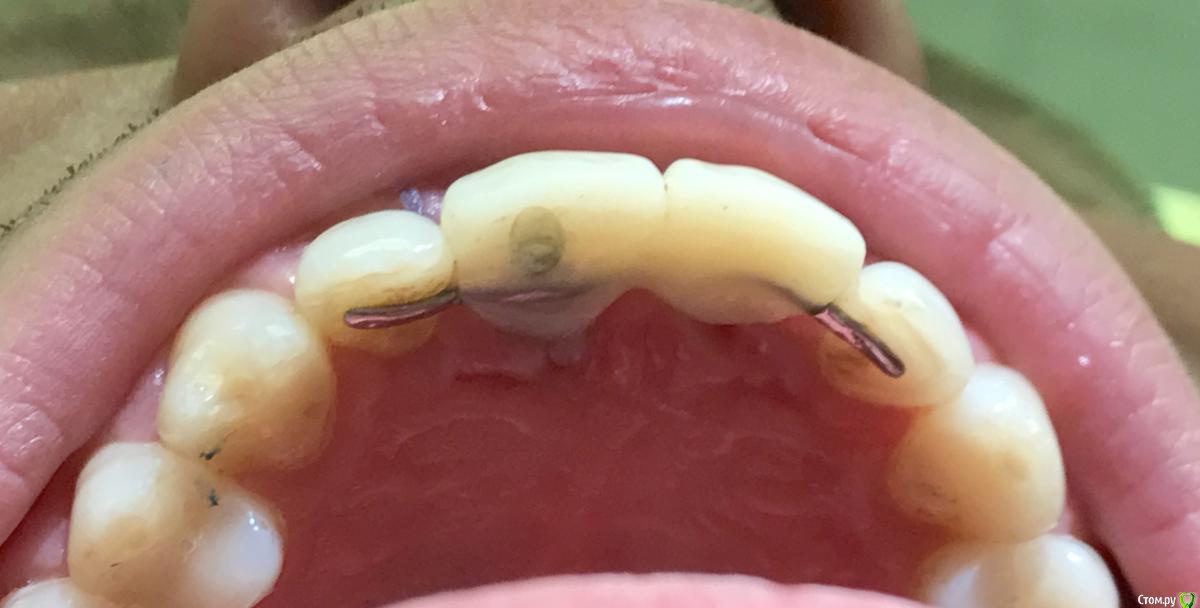

колесников Опубликовано 25 октября, 2017 Поделиться Опубликовано 25 октября, 2017 Лучше с нагрузкой. Сразу понятна будет позиция импланта относительно окончательной реставрации,если что -то не понравится можно пересверлиться, одновременно формируется профиль десны. Консоль с овоидом,работа получится супер. Незабудьте зашинировать к соседним зубам ,лучше армировать. Если пациент отнекивается ,не хочет тратиться на временную конструкцию,используйте имплантовод анкилос как временный абатмент. Вот как пример реставрация на имплантоводе семадос и армированный имплант с консолью. 1 Ссылка на комментарий